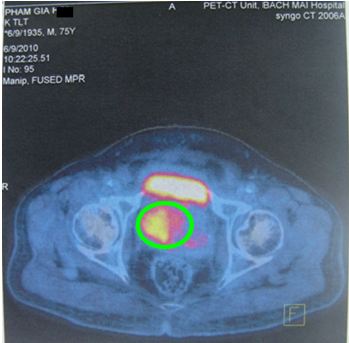

Hình dưới đây cho thấy giá trị của PET/CT trong phát hiện tổn thương tại tuyến tiền liệt.

Hình 1. Bệnh nhân Phan L. Th., nam, 75 tuổi, chẩn đoán: Ung thư tuyến tiền liệt. Trên hình CT, FDG-PET và FDG-PET/CT thấy khối u thùy trái tuyến tiền liệt tăng hấp thu FDG mạnh, max SUV=5,57.